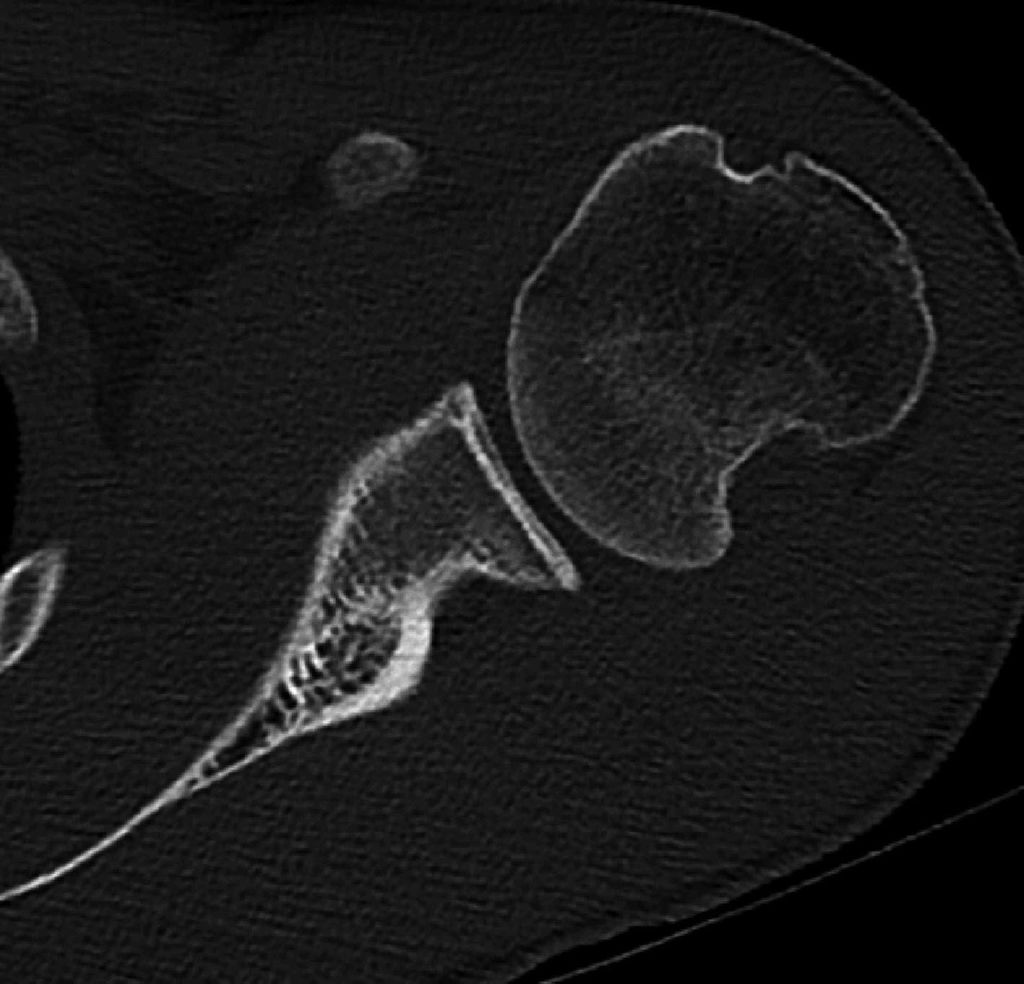

Das Risiko des Vorhandenseins von Knochendefekten am Glenoidrand wird allgemein unterschätzt, daher ist eine Computertomografie (CT) bei Rezidivinstabilitäten obligat. Insbesondere bei chronischen glenohumeralen Instabilitäten nach Voroperation sind knöcherne Läsionen nahezu immer vorhanden und es gilt, deren Größe und Lokalisation zu erfassen. Neben Standardschichtungen sollte eine 3D-Rekonstruktion des Glenoids unter Subtraktion des Humerus („en face view“) durchgeführt werden, um Pfannenranddefekte zu quantifizieren.39–41 Für die Erfassung der Größe eines Knochendefektes am Glenoid stehen verschiedene Methoden zur Verfügung.42 In den meisten Fällen wird in der „en face view“ ein „best fit circle“ zur Quantifizierung des Knochendefektes herangezogen43 (Abb. 1). Das Zentrum dieses Kreises liegt grob im Bereich des „bare spot“. Bei der Pico-Methode wird durch Überlagerung mit der gesunden Seite die Fläche des Defektes errechnet.44 Andere errechnen das Ausmaß des Defektes unter Verwendung der Distanzen zum „bare spot“.45 Außerdem wird anhand der CT auch ermittelt, ob es sich um eine monopolare oder bipolare Läsion handelt, also auch am Humeruskopf eine relevante Läsion vorliegt, und ob eine „on-track“ oder „off-track“ Läsion vorliegt46 (Abb. 2).

Abb. 2: Anhand der CT wird auch ermittelt, ob es sich um eine monopolare oder bipolare Läsion handelt, also auch am Humeruskopf eine relevante Läsion vorliegt, und ob eine „on-track“ oder „off-track“ Läsion vorliegt